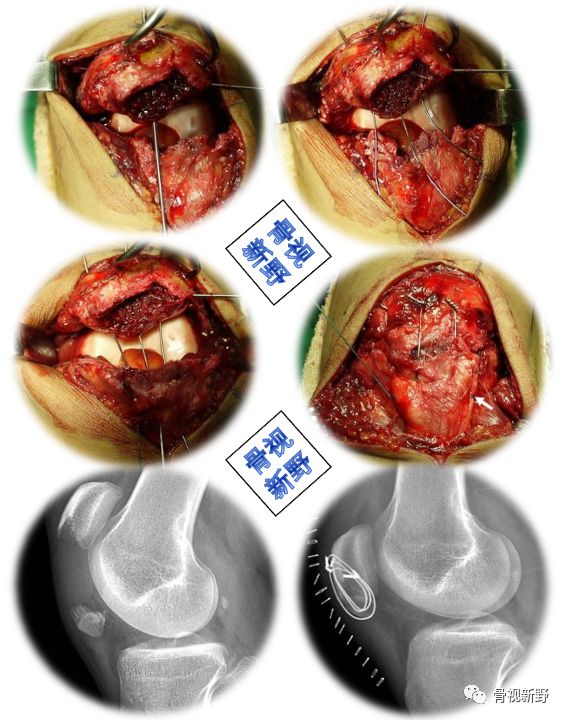

垂直钢板间断缝合+Krackow锁定式缝合

垂直钢丝间断缝合

用2-3根直径 1.2 mm的钢丝从近端骨折块的断端后表面边缘直接向髌骨前上缘穿出(或克氏针预钻孔),钢丝由内向外的方式进行穿孔;远端骨折块用16 号针从髌骨远端骨折块下端边缘穿髌韧带穿入,再将钢丝从针的开口处穿入。以复位钳钳夹及垂直钢丝的牵拉、收紧进行复位。

Krackow 锁定式缝合

间断垂直钢丝复位之后,对髌腱两侧进行连续锁边缝合(Krackow 缝合)。

可用两根抗张线(如爱惜康-5号)编织髌腱。再用2.5mm钻(或克氏针)在髌骨上做3条垂直的骨道,中间的Krackow编织环组成的两个线穿过中间骨道,剩下的内、外侧边线则穿过相应的内侧和外侧骨道。再用针将中间两个线沿髌骨上极穿过股四头肌肌腱,到内侧和外侧相应的打结位置,以减少软组织嵌入线结内。最后,在膝关节屈曲30°时测试张力和打结。